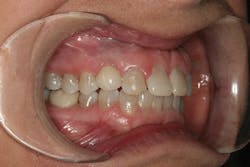

After approval of the diagnostic wax-up, profound anesthesia in the area of Nos. 6 through 11 was achieved (Septocaine, Septodont). Following sounding for bone to confirm adequate biologic width, laser soft-tissue recontouring in the areas of Nos. 6 through 11 was performed using an Er;Cr:YSGG soft- and hard-tissue laser (Waterlase, Biolase). Teeth Nos. 7, 8, 9, and 10 were prepared for conventional porcelain laminate veneers. Implant crowns were sectioned and removed from Nos. 6 and 11 (figure 4). To verify the radiographic implant identification, the abutments were removed and impression copings were tried in and radiographic seat was confirmed. The abutments were then replaced to serve as provisional restorative components. Screw access holes were blocked out and the provisional stent was used to fabricate provisional restorations on Nos. 6 through 11 (Luxatemp Ultra BL, DMG America) (figures 5, 6).

Figure 4

Figure 5

Figure 6